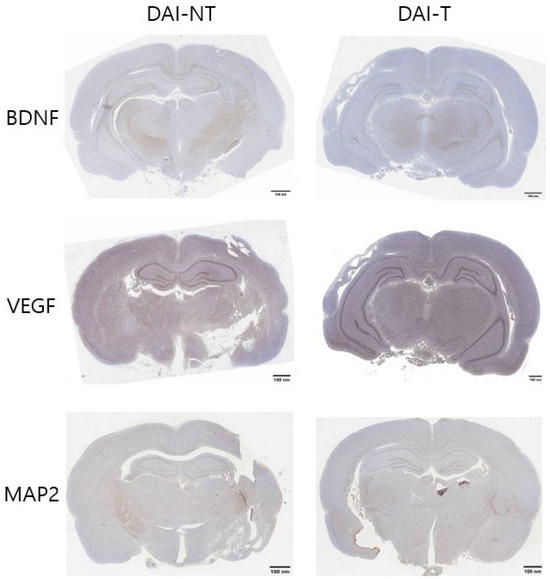

4.3. Immunohistochemistry

| Immunohistochemistry | Group | Area | Mean | % Area |

|---|---|---|---|---|

| BDNF | DAI-NT | 1,654,224 | 202.597 | 5.008 |

| DAI-T | 1,654,224 | 192.308 | 8.778 | |

| VEGF | DAI-NT | 1,654,224 | 168.547 | 8.711 |

| DAI-T | 1,654,224 | 158.346 | 12.105 | |

| MAP2 | DAI-NT | 1,654,224 | 204.679 | 10.475 |

| DAI-T | 1,654,224 | 202.148 | 12.814 |